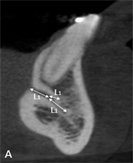

The following measurements were performed: longest width of the genial canal (W) or (D); longest length of the genial canal in relation to the alveolar bone crest (L) or (L1); (D1) or (L2), which was performed between the uppermost portion of the genial plexus and the alveolar bone crest (for dentate patients the reference was the buccal bone crest); shortest distance from the genial plexus to the buccal cortical bone (D2) or (L3), which was performed between the most vestibular portion of the genial plexus and the buccal cortical bone; (D3) or (L4), which was performed between the lowest portion of the genial plexus and the cortical part of the mandible base (Figures 1(B)-(D)).

Figure 1. Tomographic images, diameters and distances of the canal and plexus. (A) Parasagittal tomographic image; (B) Canal diameter; (C) Distance from the genial plexus to the cortical bone; (D) Initial parasagittal tomographic image, central incisor tooth. Source: Own Authorship. Caption: Parasagittal tomographic image measuring the length (A) canal diameter (B) and distances as follows: (L1) of the genial canal; (L2) distance from the genial plexus to the alveolar bone crest, (L3) distance from the genial plexus to the buccal cortical bone and the base of the mandible (L4) (C), initial parasagittal tomographic image (D). Figure 1 (A) Parasagittal section of the CBCT used to perform measurements. (B) Longest width of the genial canal (W). (C) longest length of the genial canal (L). (D) Shortest distance from the genial plexus to the alveolar bone crest (D1); shortest distance from the genial plexus to the buccal cortical bone (D2); shortest distance from the genial canal relative to the base of the mandible (D3).